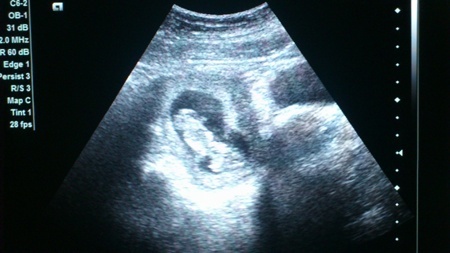

11. hét és végre történések vannak. Voltam orvosnál, a harmadiknál –nála voltak a legkevesebben aznap, így csak másfél órát kellett várni-, és elképesztőem kedves volt. A férjem az ajtó előtt várt, amíg beszéltem az orvossal, mondtam neki, hogy a terhesség 12. hetében járunk, de a magzati kor ugye 10 hét. Erre azt mondta, hogy azért kukkantsunk be a pocakba, hogy mi újság és, hogy mekkora a magzat. Kérdésemre, hogy bejöhet-e a férjem, azt mondta, hogy természetesen, úgyhogy Mr. Mimi gyorsan, magabiztosan bejött a vizsgálóba.

Az orvos előre jelezte, hogy sajnos képet adni nem tud, de ha van nálunk telefon, nyugodtan lehet képeket készíteni. Mr. Mimi elő is kapta a mobilját és kellő távolságból, nem rámászva a dokira próbált aránylag éles, jól kivehető képeket készíteni.

Az orvos nagyon kedves volt, többször ki is merevítette a képet és végig magyarázott, hogy mit is látunk éppen. Én aránylag sajnos keveset láttam belőle, de azért a buksiját, a kezeit és a lábait egy-egy pillanatra láthattam. A térdkalácsot viszont akárhogy bandzsítottam és fókuszáltam, nem tudtam felismerni, és mint utólag kiderült, Mr. Mimi sem, de legalább tudjuk, hogy van térdkalácsa is.

Pontos méreteket sajnos nem mondott, de két hét múlva megyünk a genetikai ultrahangra, akkor úgyis többet fogjuk nézegetni a babát és a méreteivel is többet fogunk foglalkozni. A doki egyébként azt azért hozzátette, hogy nagyobb, mint egy 10 hetes magzat, inkább 11 hetesnek mondaná.